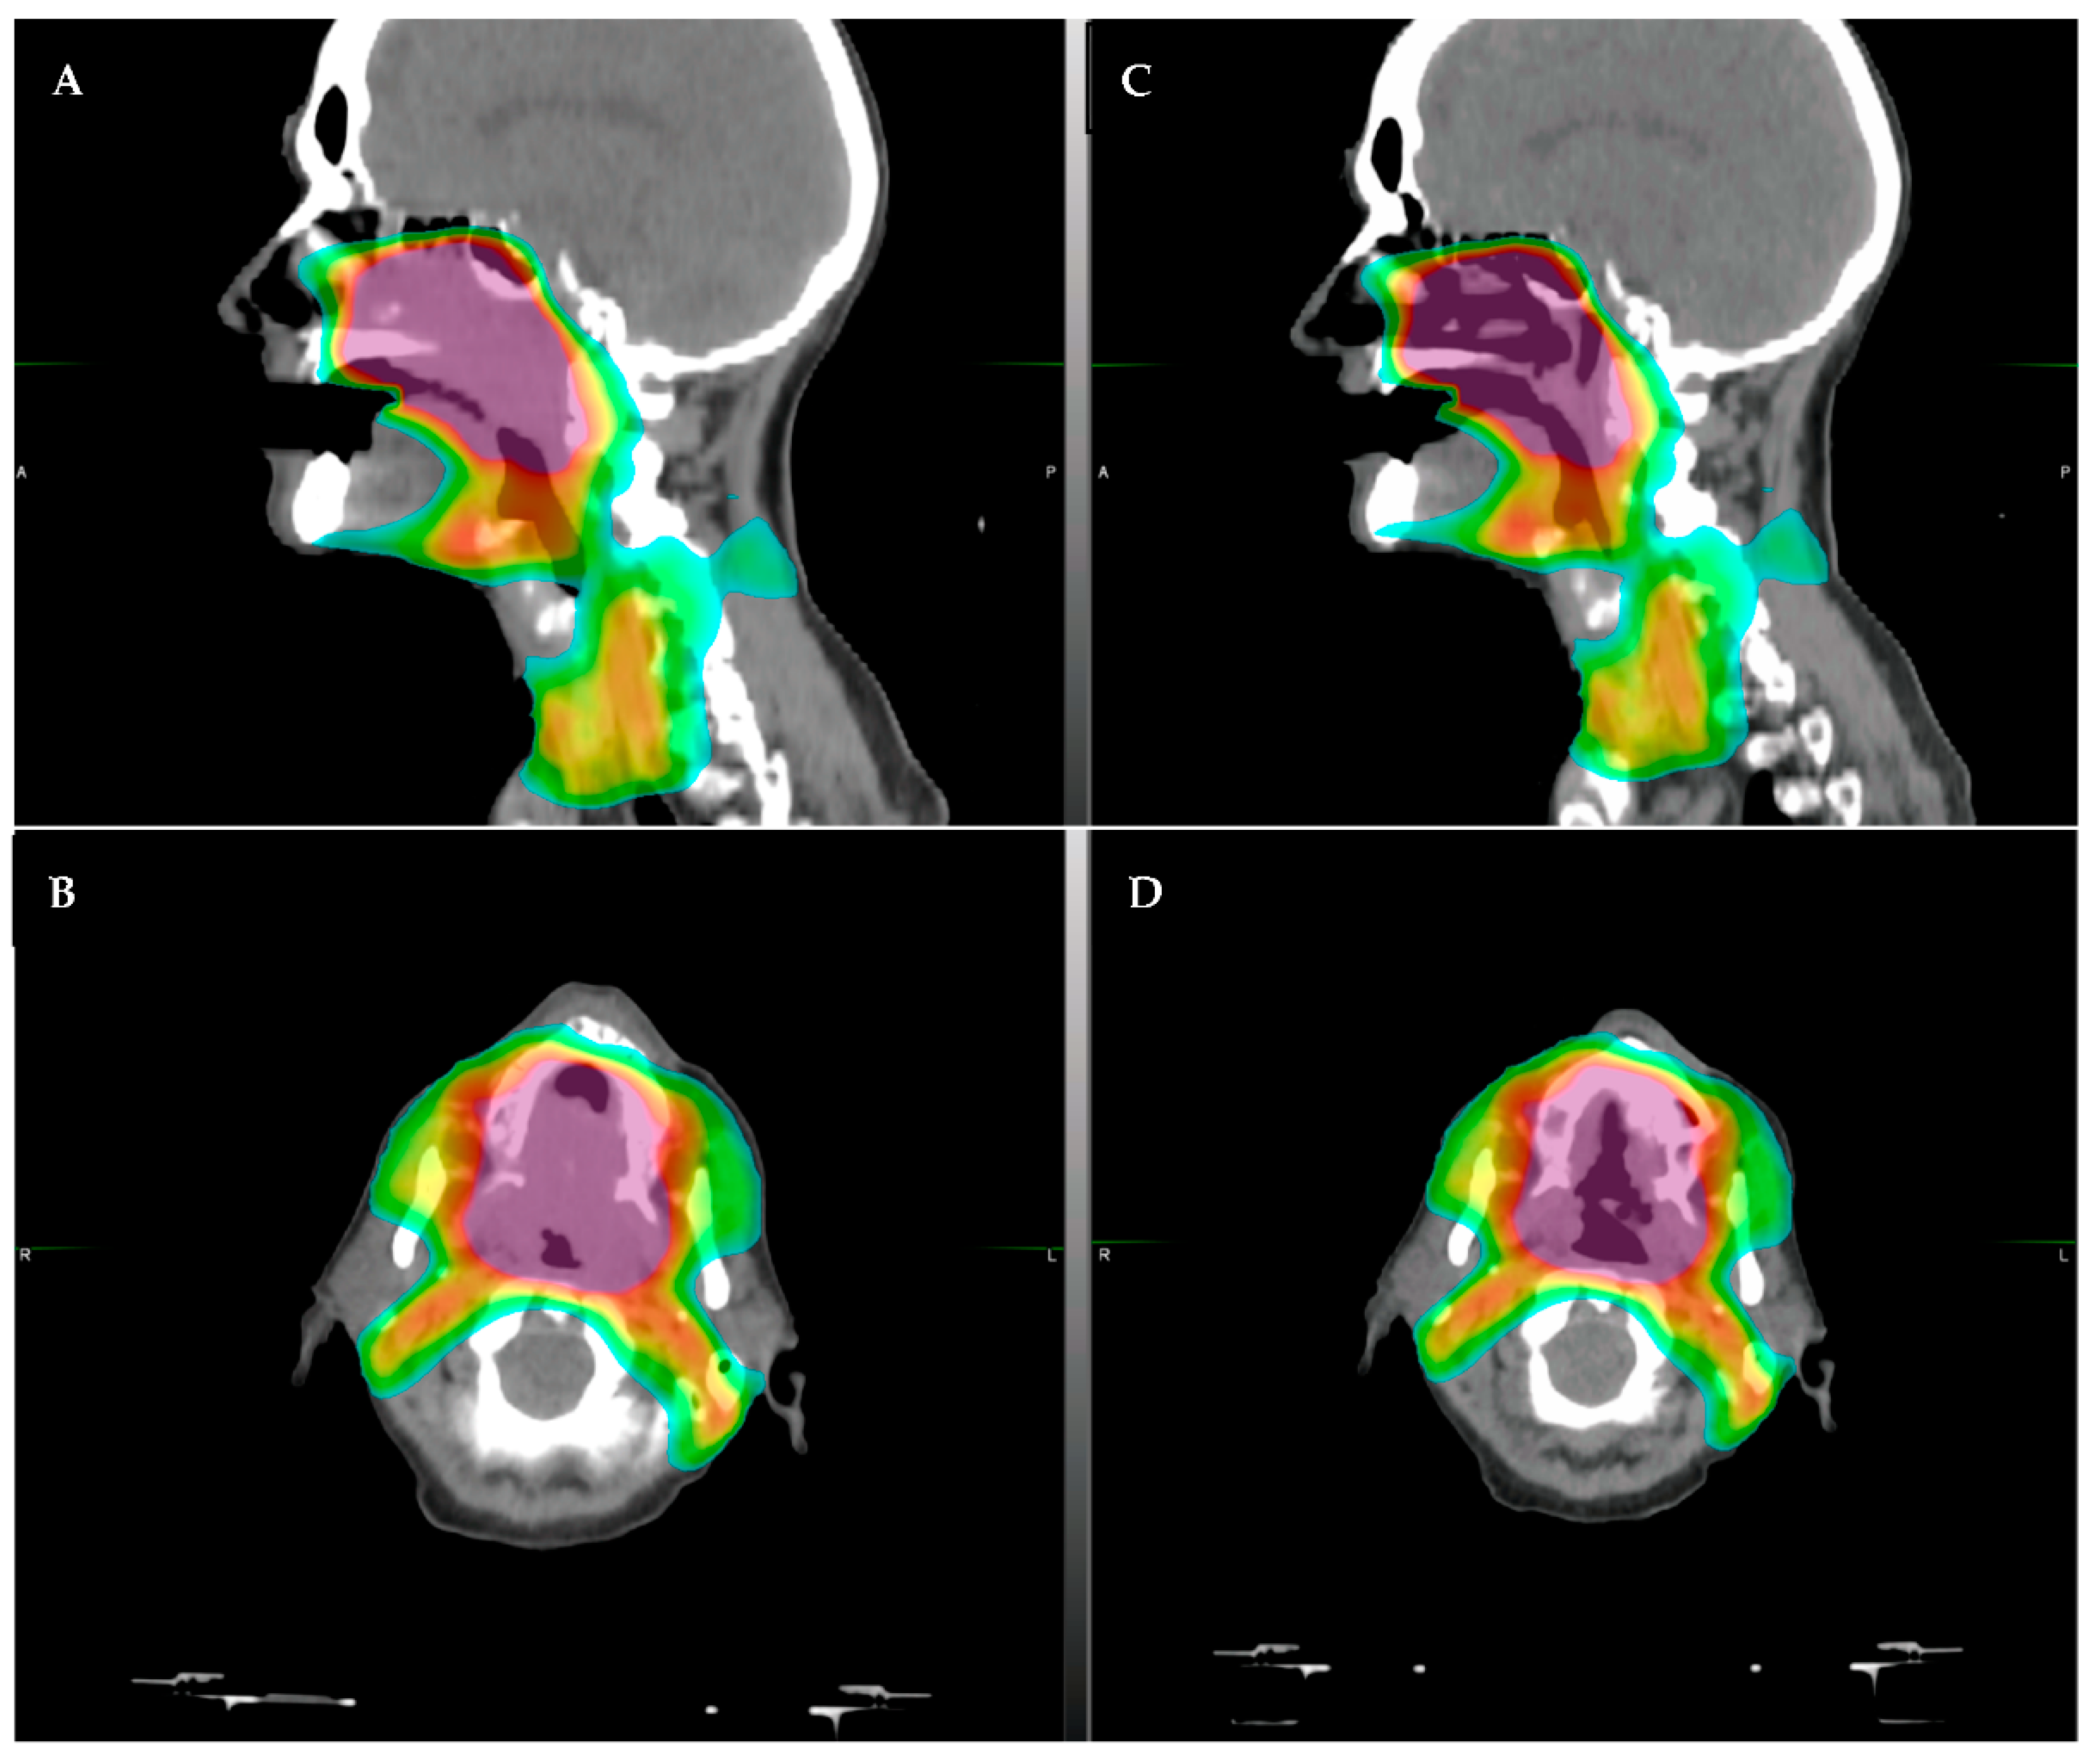

- McDonald, B.A.; Vedam, S.; Yang, J.; Wang, J.; Castillo, P.; Lee, B.; Sobremonte, A.; Ahmed, S.; Ding, Y.; Mohamed, A.S.; et al. Initial Feasibility and Clinical Implementation of Daily MR-Guided Adaptive Head and Neck Cancer Radiation Therapy on a 1.5 T MR-Linac System: Prospective R-IDEAL 2a/2b Systematic Clinical Evaluation of Technical Innovation. Int. J. Radiat. Oncol. 2020, 109, 1606–1618. [Google Scholar] [CrossRef] [PubMed]

- Bahig, H.; Yuan, Y.; Mohamed, A.; Brock, K.K.; Ng, S.P.; Wang, J.; Ding, Y.; Hutcheson, K.; McCulloch, M.; Balter, P.A.; et al. Magnetic Resonance-based Response Assessment and Dose Adaptation in Human Papilloma Virus Positive Tumors of the Oropharynx treated with Radiotherapy (MR-ADAPTOR): An R-IDEAL stage 2a-2b/Bayesian phase II trial. Clin. Transl. Radiat. Oncol. 2018, 13, 19–23. [Google Scholar] [CrossRef] [Green Version]